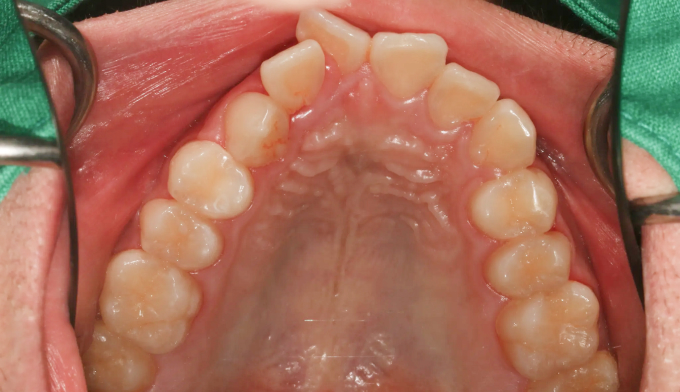

불규칙앞니

불규칙한 앞니를 교정하기 위해선 공간을 만들어야 합니다.

악궁이 좁은 경우에는 확장치료를, 그렇지 않으면 전체 치아를 후방이동시키거나 치아를 삭제하기도 합니다.

이번에는 악궁이 좁은 경우에 해당됩니다. 그 정도가 심해, 윗니 일부가 아랫니보다 안쪽으로 들어가있습니다.

상악확장장치를 통해 악궁을 넓혀주고 치아를 배열해줍니다.

치료기간은 15개월 소요되었습니다.